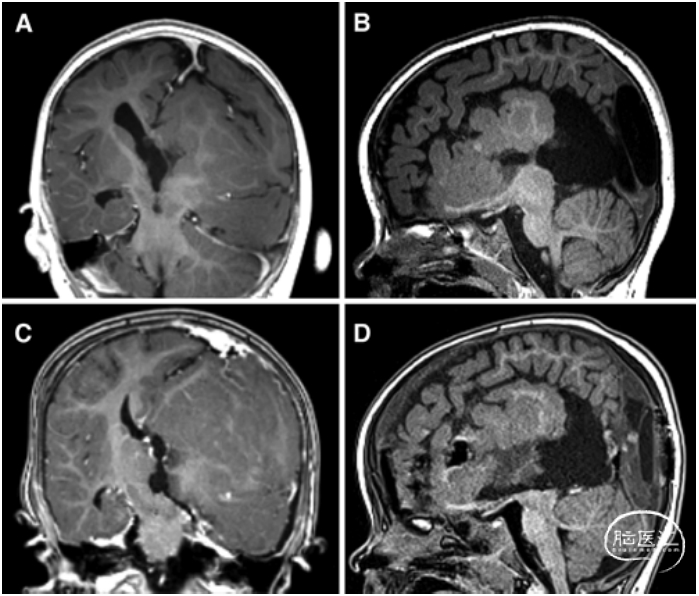

图1. MRI-T1加权增强冠状位成像和T1加权矢状位成像;A和B为术前,C和D为术后改变。A.大脑镰与半球间隙成角;经顶入路,转向患侧小脑幕。B.左侧矢状窦旁成像显示,额叶与左视束关系紧密;分离额叶和左侧视神经时,以视神经作为关键解剖标志。C.从三脑室到小脑幕分离丘脑与中脑。D.中脑喙部与视束上方离断。